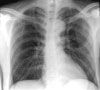

The patient is oriented to person only but follows commands. Temperature is 38.9°C (102.1°F); blood pressure, 136/73 mm Hg; heart rate, 81 beats per minute; respiration rate, 22 breaths per minute; and oxygen saturation, 97% on room air. Pulmonary and cardiac findings are unremarkable. The abdomen is soft and nontender. There is no peripheral edema. Neurological findings are nonfocal. A chest radiograph obtained as part of a fever workup is shown.

Answer: Miliary tuberculosisDiscussion: This chest radiograph shows a miliary pattern, which may occur during post-primary tuberculosis (TB). At this stage of the disease, hematogenous spread to the pulmonary parenchyma results in 1- to 2-mm nodules that resemble millet seeds (shown here) throughout both lungs. In the past, the term "miliary" was more of a radiographic description; it now refers to all cases of disseminated hematogenous tuberculosis.1

The differential diagnosis of a miliary pattern on a chest radiograph is broad (Table).1 Nontuberculous causes may include any granulomatous or neoplastic disease. Small, well-demarcated lesions usually represent thickening of the interstitium of the lung. Lesions that are the same size are generally granulomas.